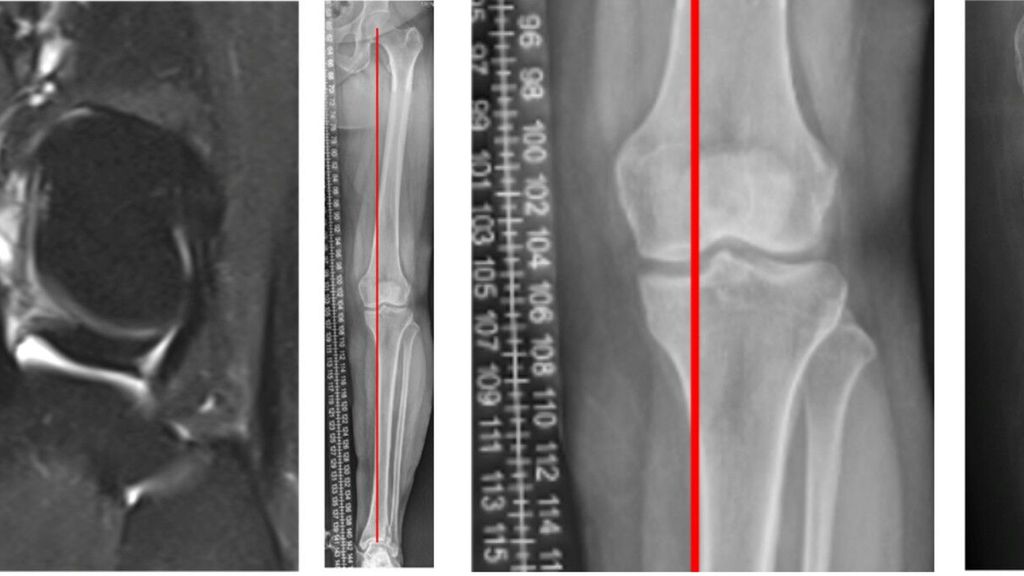

Behrendt stellte im Zuge seines Vortrags den Fall einer 25 Jahre alten Handballspielerin mit Distorsionstrauma im Mai 2023 vor. Bei einer MR-gestützten Partialruptur des vorderen Kreuzbandes mit geringer subjektiver Instabilität wurde zunächst konservativ behandelt. Im Verlauf zeigten sich jedoch zunehmende Hyperintensität am Innenmeniskus-Hinterhorn und eine Restinstabilität beim Handballspielen. Ein Jahr nach dem Unfall führte die zunehmende Symptomatik zu einem klaren Meniskusriss, sodass eine Kreuzbandersatzplastik und eine Rekonstruktion des Innenmeniskusrisses durchgeführt wurden (Abb.1). Diese Fallvignette verdeutlicht, dass nach unzureichender Versorgung eines vorderen Kreuzbandrisses das Risiko für zusätzliche Meniskus- und Knorpelschäden hoch ist. Eine Metaanalyse zeigte, dass dies in 88 % der Studien (35 von 44) auftrat. Kritische Zeitgrenzen lagen bei sechs Monaten für Meniskus- und zwölf Monaten für Knorpelschäden; danach stieg die Wahrscheinlichkeit weiterer Schädigungen deutlich an. Mit zunehmendem zeitlichem Abstand zum Kreuzbandriss verschlechtert sich zudem die Rekonstruierbarkeit der Menisken.8